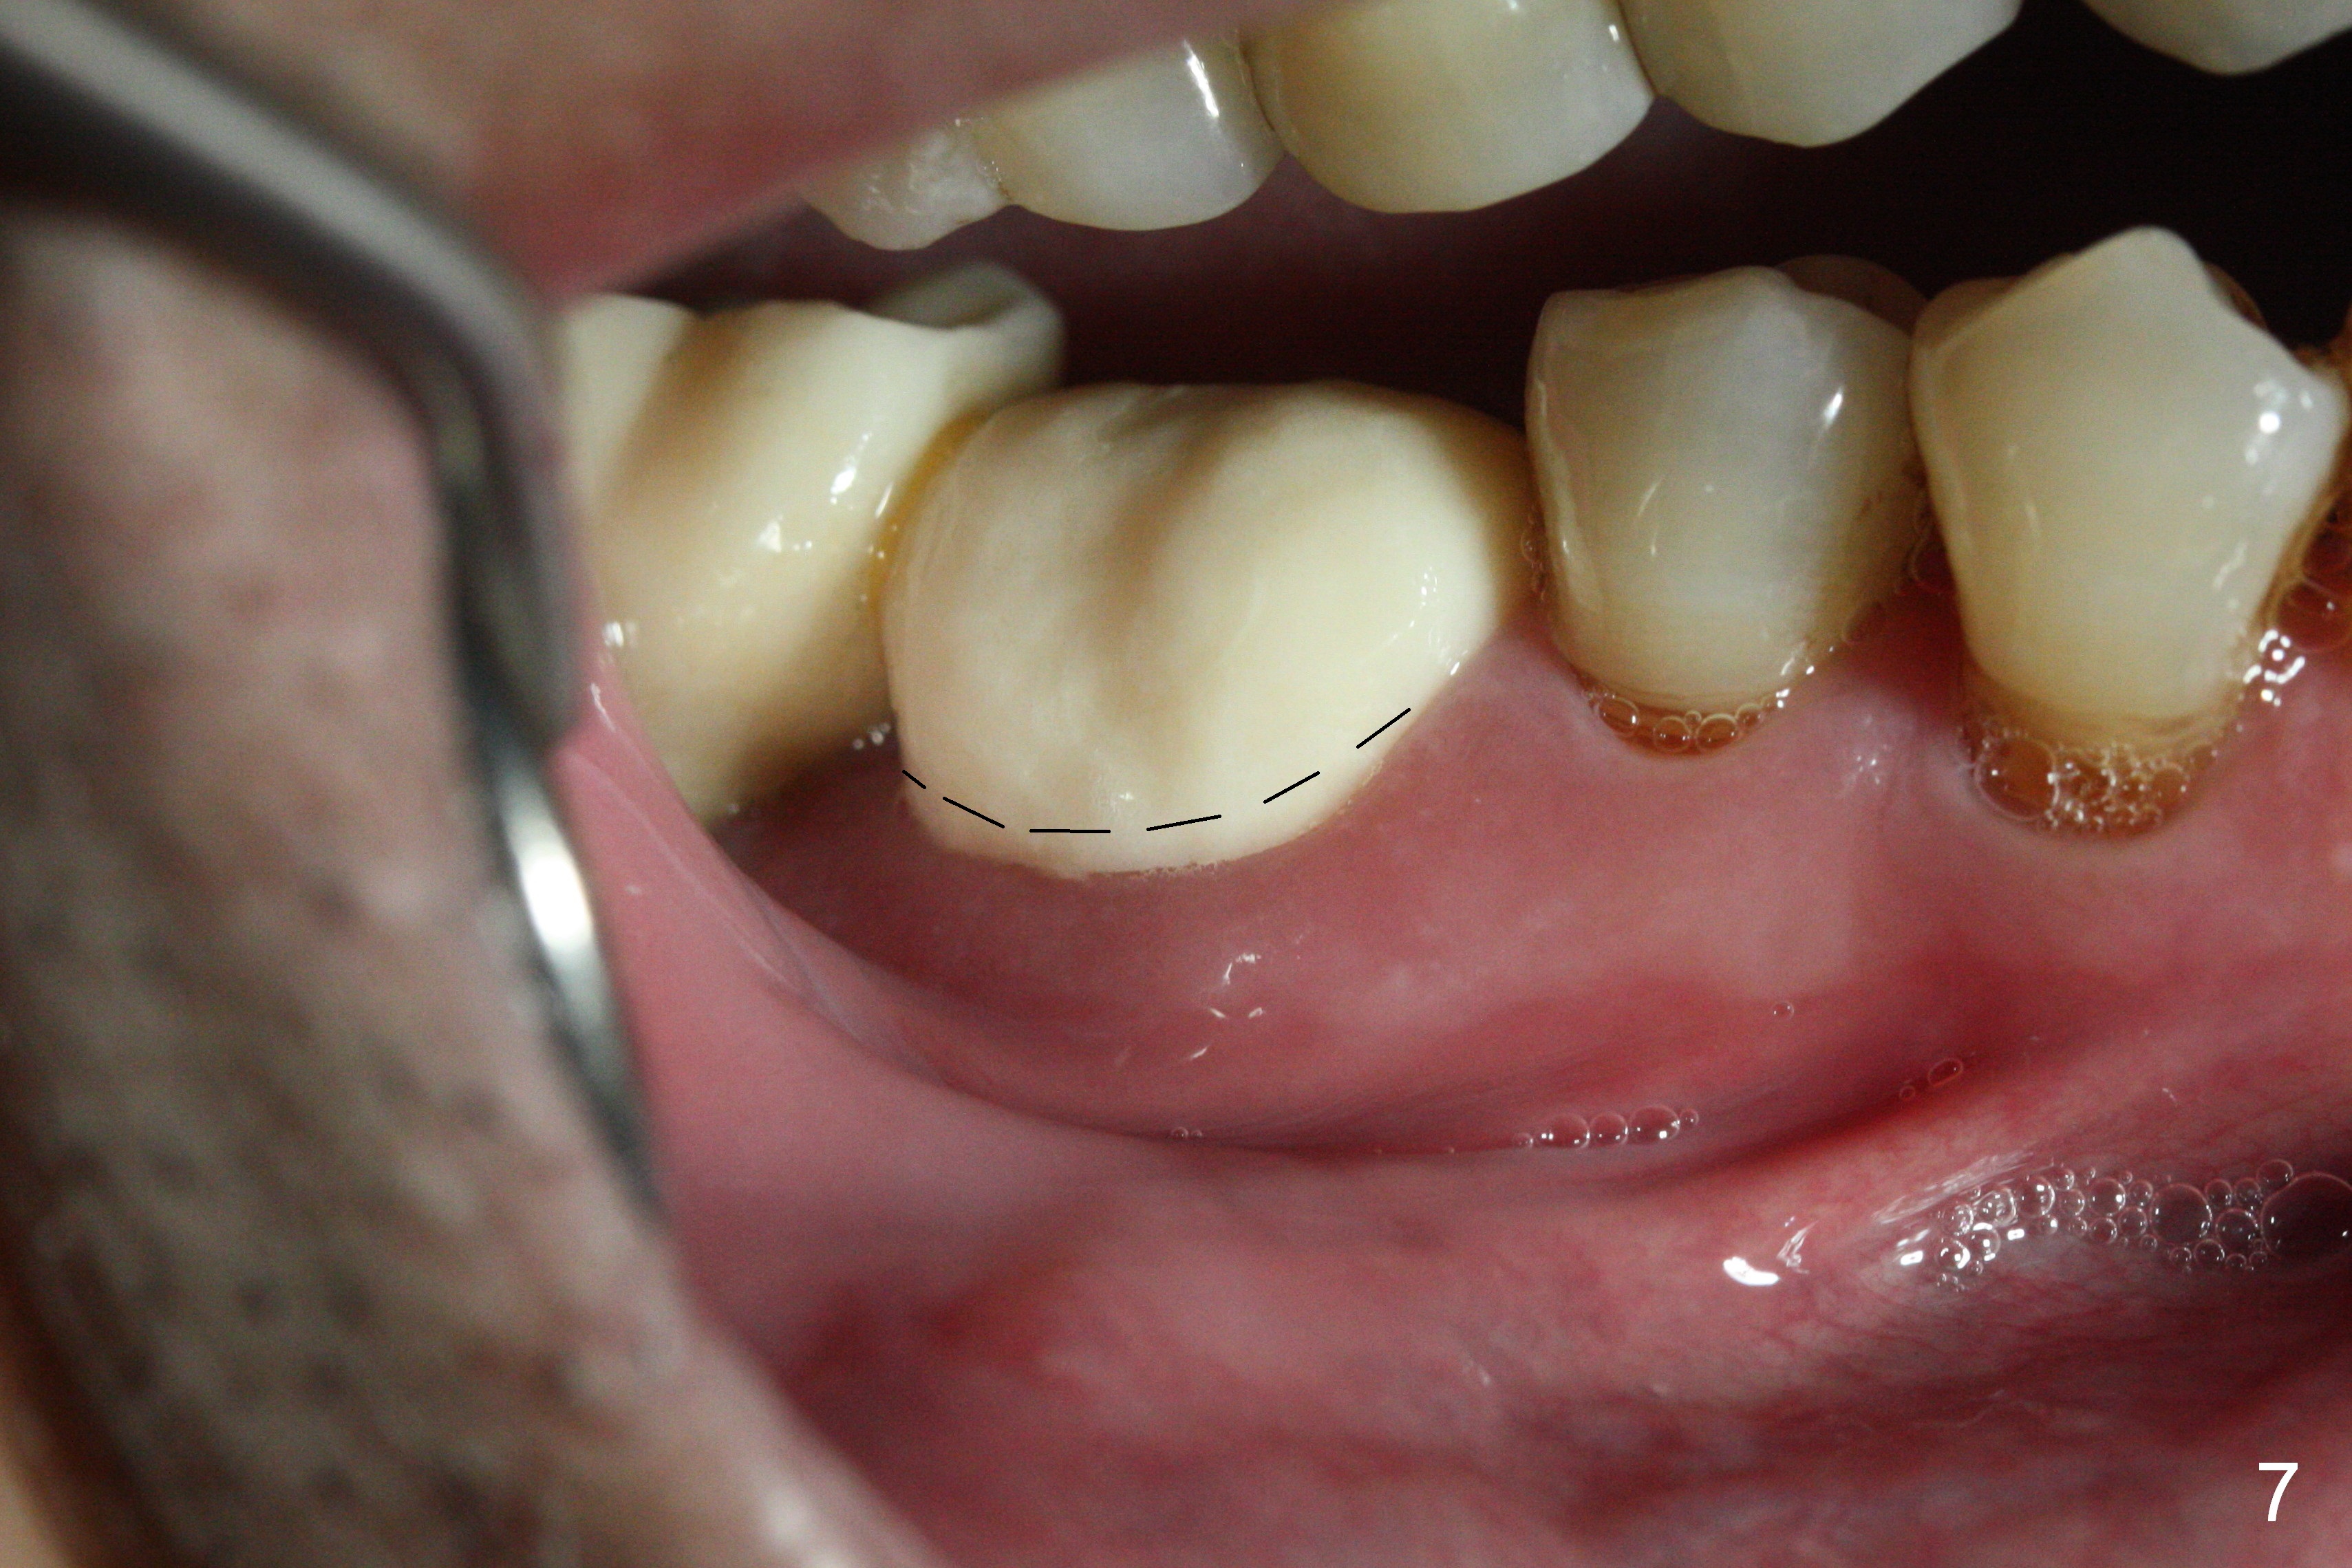

Extraction shows the large distal socket (Fig.1 D) and the thin and low septum (*) of the tooth #30. After Magic Split test confirms hard bone, osteotomy is initiated with 1.6 mm pilot drill with 11 mm stopper (Fig.2); there is 2.7 mm distance to the Inferior Alveolar Canal. Following Marking Bur, a 4.8 mm Magic Drill is used to finish the osteotomy with difficulty because of hard bone and ineffective local anesthesia due to infection. A 5x9 mm "dummy" implant is placed to determine the placement level relative to the distal crest (Fig.3 *). After removal of the dummy implant, an authentic one with the same dimension is placed with packing abundant allograft (.5-1.5 mm) and Osteogen (Fig.4 *); it appears that 4 to 5 threads (fins) of the implant (arrowheads) are engaged to the native bone for primary stability (>40 Ncm). Later more bone graft is placed distally (Fig.5 arrow). With the short implant placed not so deep, there is 6-7 mm clearance from the underlying canal (Fig.6). The patient is doing well 7 days postop (Fig.7). He feels that the provisional is too bulky buccally for the first 2 days postop. The buccal margin will be trimmed in another 2 weeks (dashed line). The patient in fact masticates on the right side postop. By the time he returns for provisional revision 1 months 10 days postop, he has mild pain. There is food entrapment. The provisional and the abutment are slightly loose, whereas the implant is stable with healing socket (Fig.8). A healing abutment is placed. The implant appears unstable nearly 5.5 months postop. The gap between the bone and implant seems to be large (Fig.9). The implant should have been larger and longer for fast healing. A healing screw is used instead. The site heals 10 months postop with an increase in bone density around the implant (Fig.10.) Prior to cementation of the final crown, the abutment is minimally exposed (Fig.11 (6.5x5.7(3) mm)). In fact the abutment screw becomes loose 2 months post cementation (1 year postop); it appears that crown/implant ratio is unfavorable (Fig.12). The implant is slightly placed mesially (cantilever). The patient cannot chew on the left. The tooth #19 is periodontally affected and the tooth #18 is missing. When bone loss is severe, the implant should be as large as possible and preferably tissue-level. The abutment screw is re-loosening 1.5 years post cementation (4 months post #19 socket preservation, Fig.13). The crown/implant ratio at #31 is more favorable than that at #30 (compare black lines). The crown at #31 has large contact area with the tissue-level implant (external), whereas the contact between the abutment and the bone-level implant is much less (internal). To prevent the abutment screw re-loosening (turning) in function, a screw driver (Fig.14 D) will be buried inside the crown/abutment after the screw is retightened. Make sure that the driver is in the middle of the access hole. Section the driver in situ obliquely (Fig.15); flat sectioning allows the driver to turn with the abutment screw in function. After insertion of plumber tape around the sectioned screw driver, use composite to fix the driver in place and seal the access hole (Fig.16). Occlusal check suggests weak link between the abutment and bone-level implant at #30.